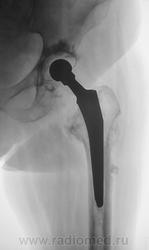

Шарнирный эндопротез. Пластиковая чашка установлена (по-моему правильно) в очищенной от суставного хряща вертлужной впадине и зафиксирована при помощи костного цемента. Ножка протеза в порядке. Какие-то остеофиты на латеральном контуре бедра (мелко: плохо видно).